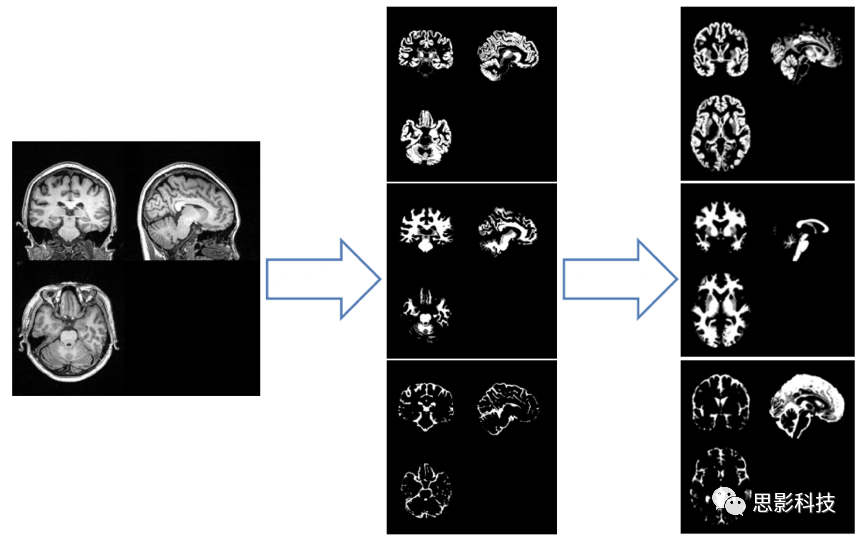

二、基于體素的形態(tài)學測量分析(VBM

基于先進的圖像分割/配準算法,可以為您精確計算多種體積指標。

1.組織分割。基于DARTEL方法,將結構像分割為灰質(zhì)、白質(zhì)、腦脊液。

2.空間標準化、調(diào)制。將灰質(zhì)、白質(zhì)、腦脊液圖像配準到標準腦模板空間;隨后基于配準生成的形變場,對圖像進行調(diào)制,生成灰質(zhì)體積、白質(zhì)體積等指標圖;不經(jīng)過調(diào)制,可生成灰質(zhì)密度、白質(zhì)密度等指標圖。除此之外,也可計算灰質(zhì)總體積、白質(zhì)總體積、顱內(nèi)總體積、灰質(zhì)總體積/顱內(nèi)總體積比值、白質(zhì)總體積/顱內(nèi)總體積比值等綜合指標。

圖示. VBM計算流程(組織分割、空間標準化)